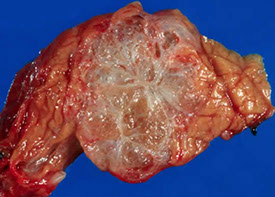

Serous (microcystic) cystadenoma

MC in women; also assoc c vHL, head of pancreas

Gross: so many little cysts looks like a well-circumscribed sponge

- MC in body / tail; often has a central stellate scar

- large size and location in the head predict aggressive behavior

Imaging: pancreatic head, has typical "honey-comb" appearance 2/2 large numbers of cystic spaces

Micro: Simple cuboidal epithelial layer filled c glycogen (clear-cells)

IHC: (+) alpha-inhibin, CAM5.2, CK7/8/18/19, MUC6, EMA (1/3), calponin

Px: Benign, does not recur